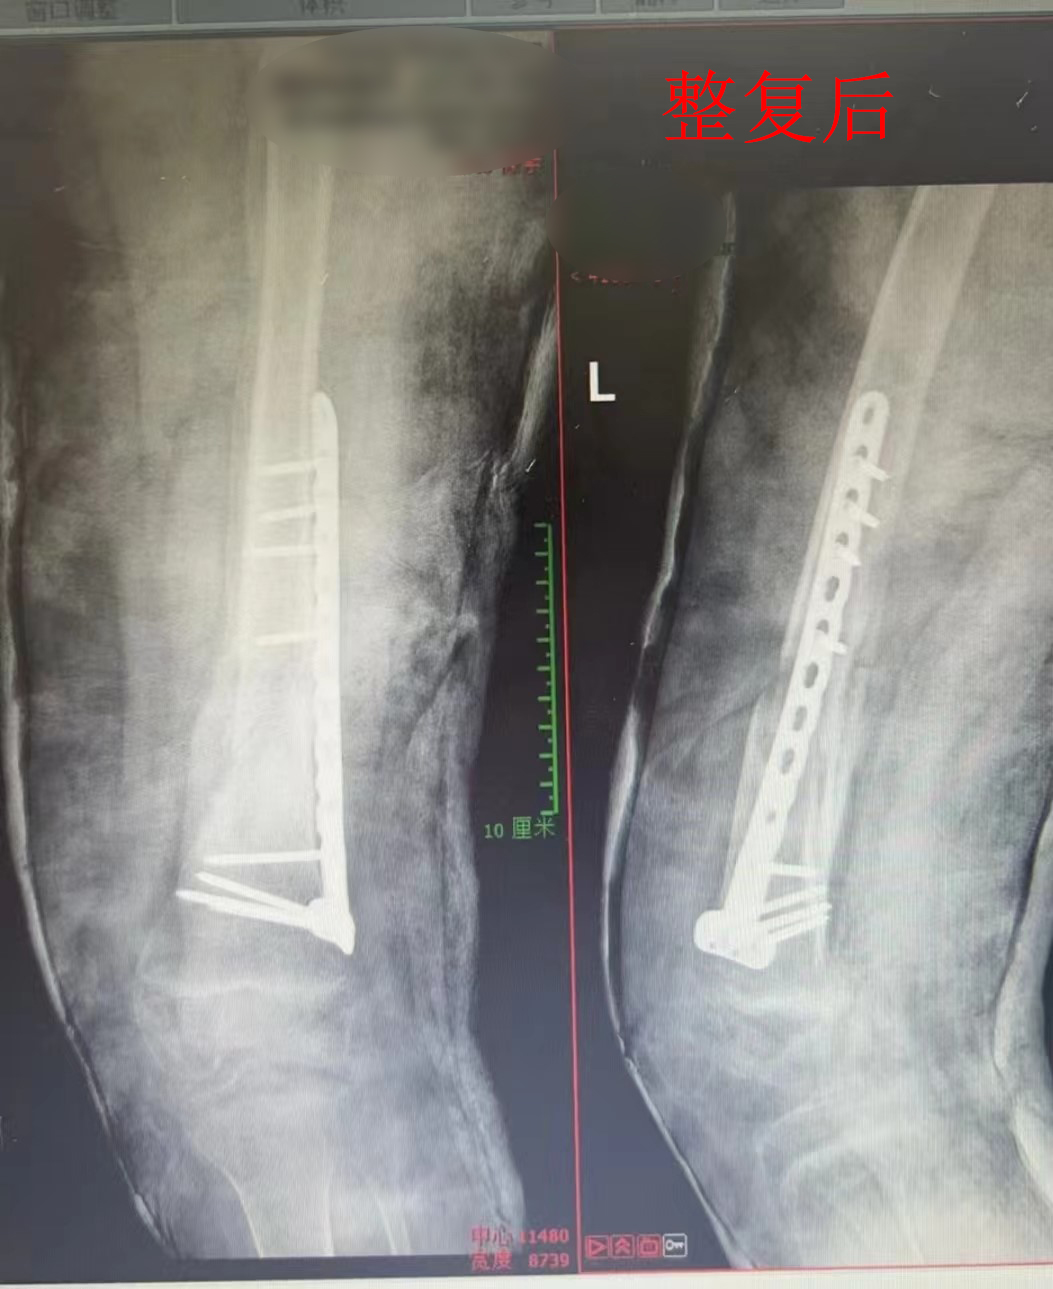

面对家属的信任,万富安主任团队精心为患儿设计治疗方案,在透视下与吕秉舒医生通过手法整复复位,使患儿骨折钢板复位良好。看到患儿一家人竖起的大拇指,万主任和他的团队感到由衷的欣慰。整复后,为患儿使用髋人字石膏固定,护士长带领护理团队精心照顾,患儿一天天康复,露出久违的笑脸。临出院这天,患儿家长送上锦旗和感谢信,紧紧握住医护人员的手,表达深深的谢意。